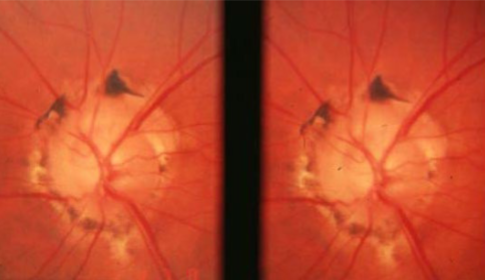

astrocytic hamartoma

congenital abnormality of astrocytes in ON & NFL

benign, non-metastasizing but may grow associated & coincident w/ growth patterns

can appear anywhere in retina but tend to be on or near disc

unilateral or bilateral

associations:

tuberous sclerosis

neurofibromatosis

appearance:

Mulberry lesions

variable size & presentation

solitary or multifocal

non-calcified or calcified

complications:

decreased vision

VF defects secondary to optic nerve compression

dx:

B-scan, FA, neuro-imaging

systemic workup

non-calcified astrocytic hamartoma

astrocytic hamartoma type

dirty white, flat, oval lesion w/ relatively smooth surface

translucent or semi-translucent

may have associated RPE changes near the lesion that resemble CHRPE

may be germinative stage of the tumor

calcified astrocytic hamartoma

whitish-yellow, elevated, multi-lobulated, mulberry lesion

non-progressive

may glisten

may be an aged version of the smooth type of lesion

astrocytic hamartoma arise in inner retinal layers & typically obscure retinal vessels, may auto-fluoresce if calcified, highly vascularized that hyperfluoresce in all FA stages

how do you differentiate astrocytic hamartoma & optic disc drusen?